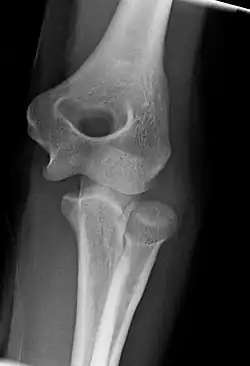

The elbow undergoes dynamic development of ossification centers through infancy and adolescence, with the order of both the appearance and fusion of the apophyseal growth centers being crucial in assessment of the pediatric elbow on radiograph, in order to distinguish a traumatic fracture or apophyseal separation from normal development. The order of appearance can be understood by the mnemonic CRITOE, referring to the capitellum, radial head, internal epicondyle, trochlea, olecranon, and external epicondyle at ages 1, 3, 5, 7, 9 and 11 years. These apophyseal centers then fuse during adolescence, with the internal epicondyle and olecranon fusing last. The ages of fusion are more variable than ossification, but normally occur at 13, 15, 17, 13, 16 and 13 years, respectively.[16] In addition, the presence of a joint effusion can be inferenced by the presence of the fat pad sign, a structure that is normally physiologically present, but pathologic when elevated by fluid, and always pathologic when posterior.[17]